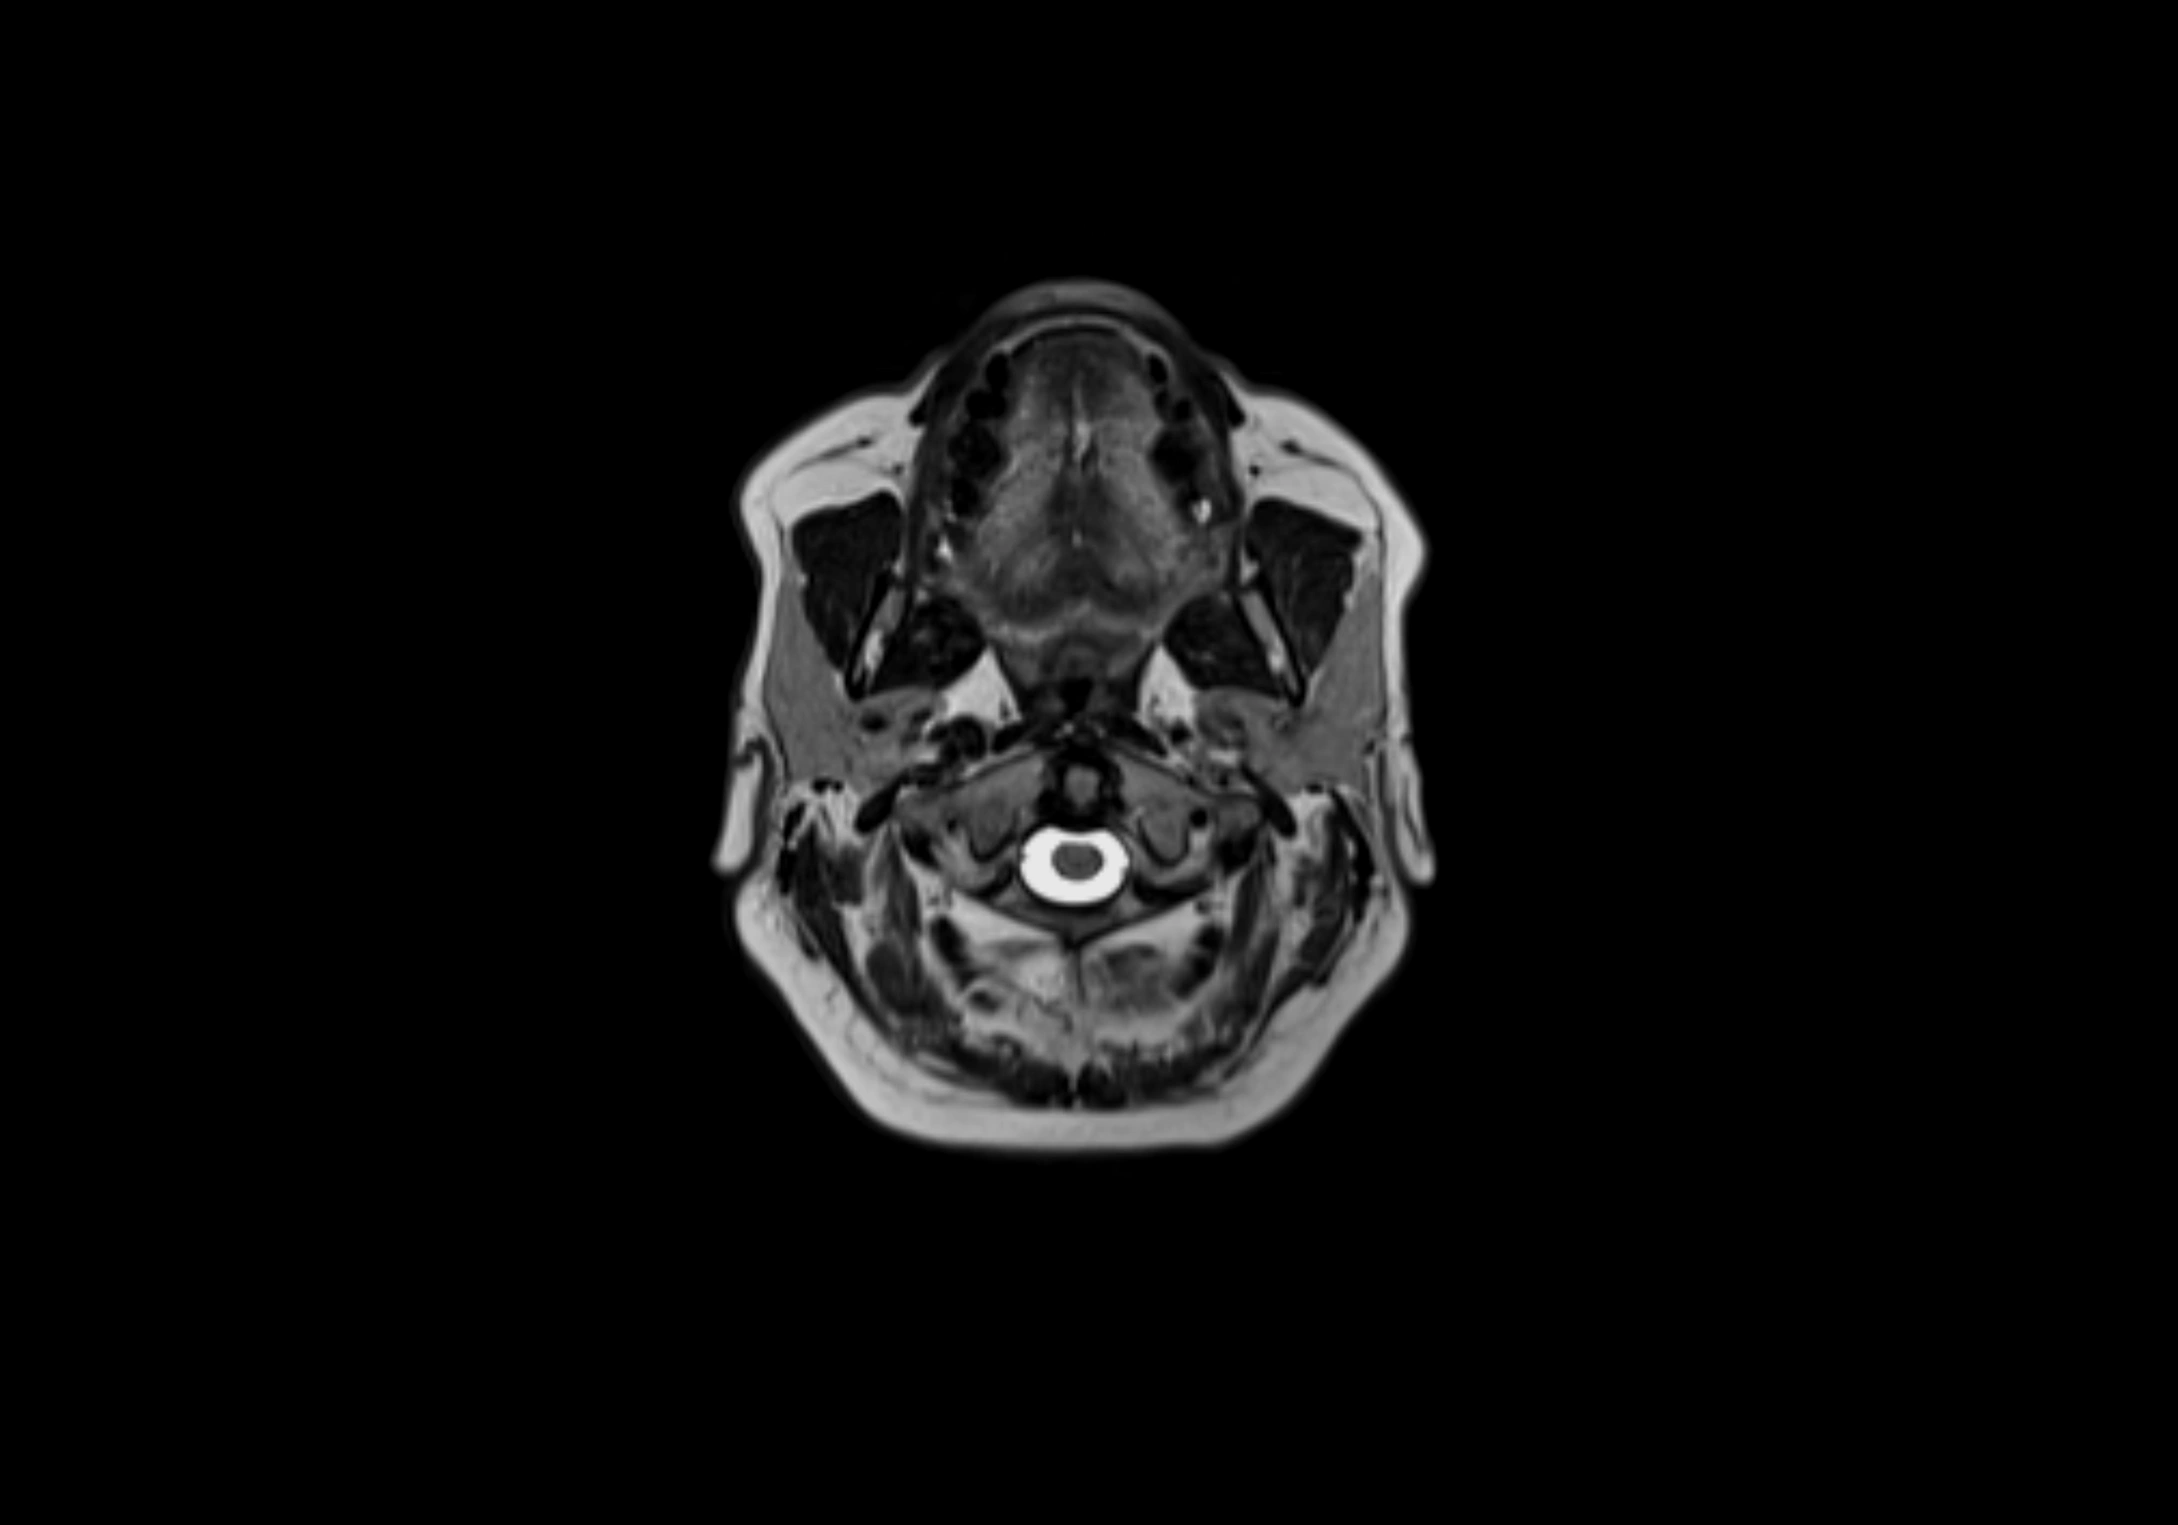

MRI Appearance

T1-weighted images:

• Normal accessory nodes appear as small, oval hypointense to intermediate signal structures within subcutaneous fat

• Surrounded by hyperintense fat, enhancing contrast for visualization

T2-weighted images:

• Nodes show intermediate signal, with surrounding fat bright

• Useful for detecting edema, inflammation, or infiltration

• Fatty hilum may appear slightly hyperintense relative to cortex